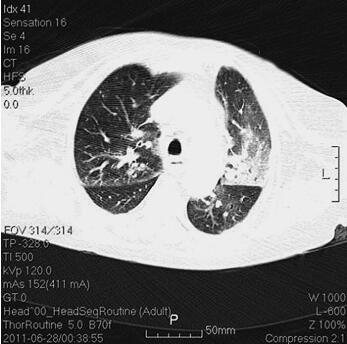

体格检查:P 85次/分,R 12次/分(机械通气),BP 121/61mmHg(多巴胺针剂维持下),T 37.3℃,SPO2 98%。神志清,精神差,气管居中,口插管在位,机械通气,颈静脉无怒张,桶状胸,两肺呼吸音粗,可闻及大量湿啰音及干啰音,心率85次/分,窦性,律齐,双下肢无明显水肿。辅助检查:胸部CT(6月28日)(图1):两肺感染性病变,两下肺支气管扩张症伴感染。心电图(6月28日):窦性心律,T波改变。血常规(6月28日):WBC 13.5×109/L,N 66.3%,Hb 145g/L;CRP(6月28日)3.8mg/L,PCT(6月28日)5.49ng/ml。

图1 胸部CT(6月28日):两肺感染性病变,两下肺支气管扩张症伴感染